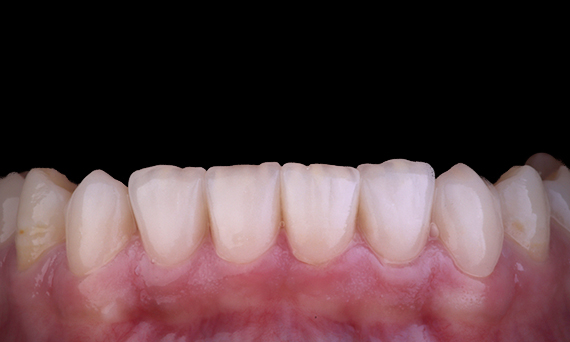

При замене верхнечелюстного центрального резца несъемным зубным протезом с опорой на имплантат залогом успеха являются выбор метода, планирование и тщательное применение методик лечения. Немедленная установка имплантатов и немедленное восстановление могут свести к минимуму потерю тканей и привести к высокоэстетичному результату. Имплантация с полным контролем может повысить точность установки, а установка окончательного абатмента или реставрации во время установки имплантата может способствовать стабильности тканей.

Доктор Алан Яп, Стоматолог-протезист, Сидней, Австралия